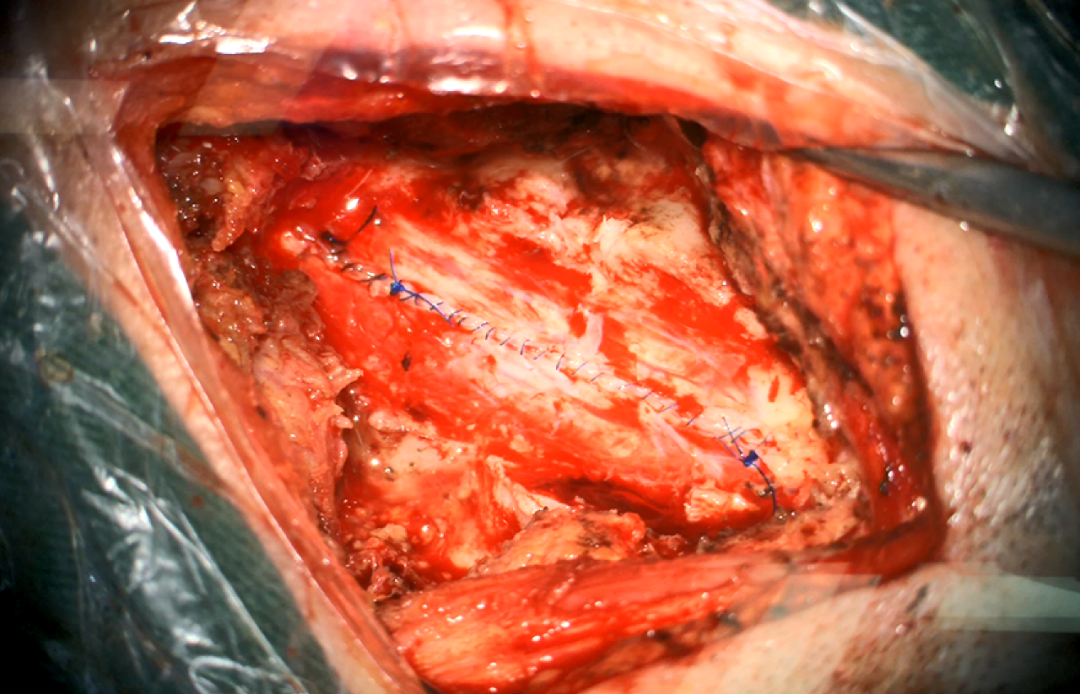

术中图片:

图8. 铣刀去除颈2-3棘突及椎板

图9. 打开硬脊膜

图10. 显露肿瘤

图11. 松解齿状韧带,进一步暴露肿瘤

图12. 分块切除肿瘤

图13. 处理肿瘤基底

14. 暴露肿瘤上极

图15. 暴露肿瘤下极

图16. 肿瘤全切

图17. 硬脊膜水密缝合

术后磁共振:肿瘤完整切除

图18. 术后患者切口愈合好,右侧肢体肌力和术前相仿,左侧肢体肌力正常,目前进一步康复锻炼治疗